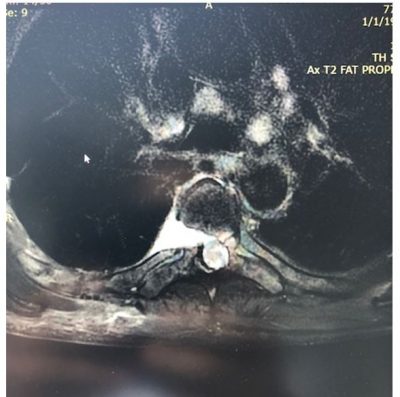

Με την πάροδο του χρόνου οι μεσοσπονδύλιοι δίσκοι μπορεί να υποστούν φθορά και να προβάλουν προς τα πίσω, πιέζοντας το νωτιαίο μυελό και τα νεύρα. Μάλιστα, συχνά, στη θωρακική μοίρα οι δισκοκήλες είναι επασβεστωμένες ή συνοδεύονται από μεγάλα οστεόφυτα (Εικόνα 1)